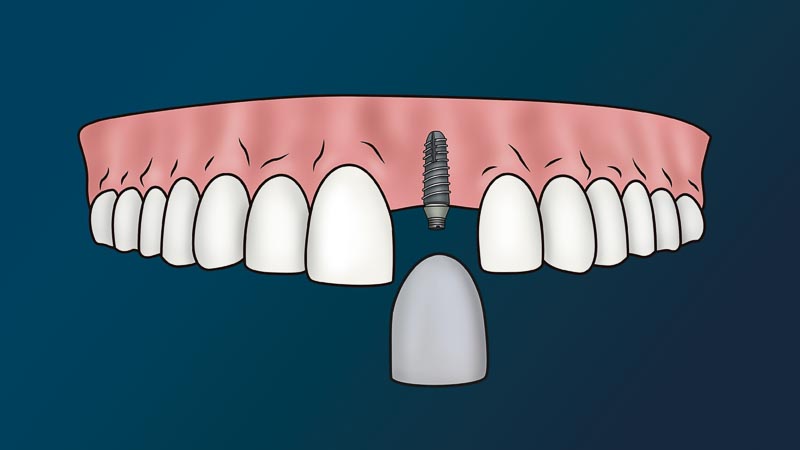

What is the Dental Implant Process in Mexico?

The dentist will attach to your jaw a metal root (implant) and place on top a fake tooth (crown). We call this procedure, a dental implant. Since this procedure is non-life threatening and non-essential to one’s immediate health, it considered a cosmetic procedure. In other words, medical or dental insurance policies don’t cover this procedure.